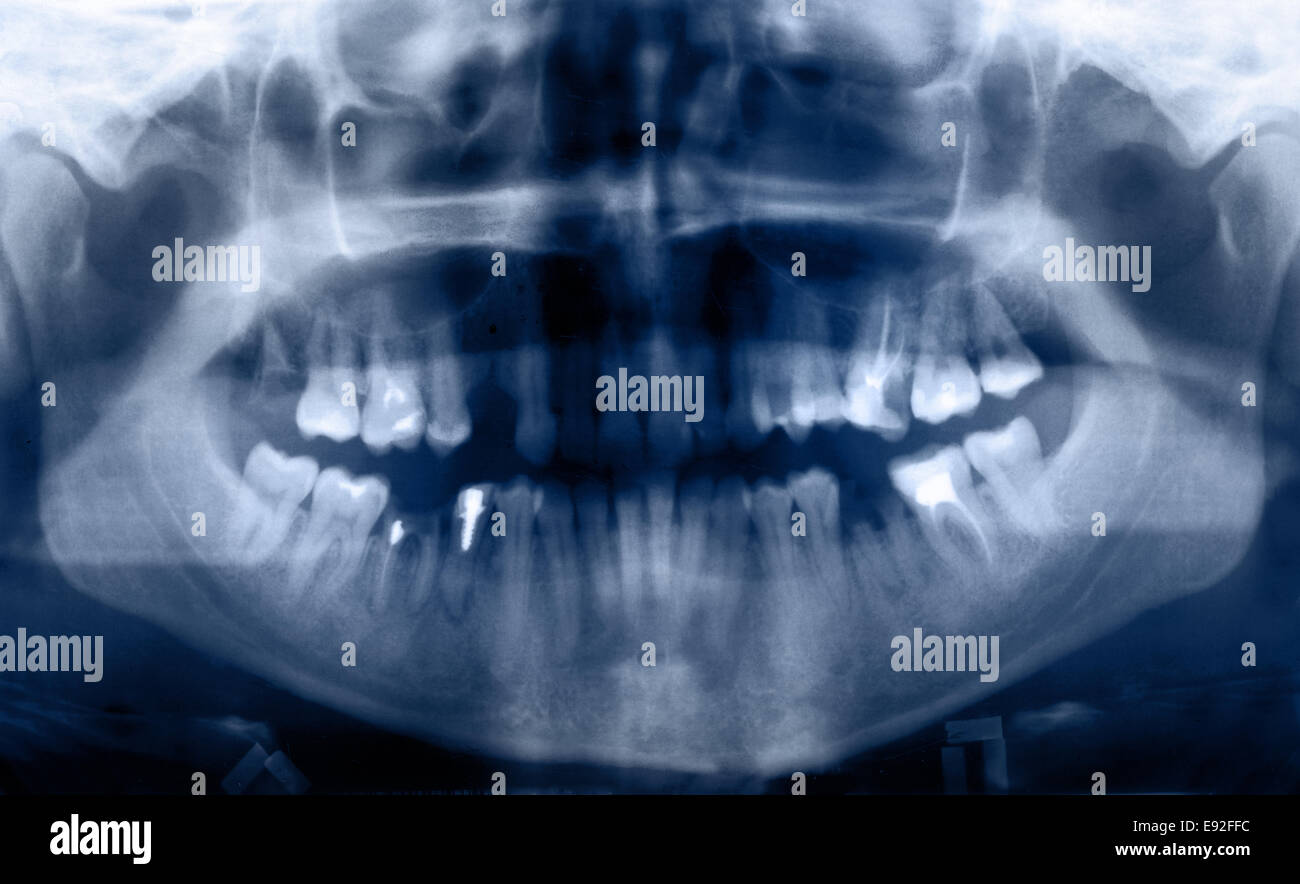

Dental Panoramic X Ray Anatomy . review normal anatomy observed in panoramic images. For the purposes of this. successful interpretation of panoramic radiographs begins with an understanding of the normal anatomy of the head and neck and how it is depicted in this image type. it is important to understand the landmarks normally seen on panoramic images in order to prevent misdiagnosis of a radiopaque or radiolucent area. It displays both jaws, the upper and lower, as well as the teeth, on the same film. This article will describe how osseous structures, soft tissues, air spaces and ghost shadows contribute to the final panoramic image. currently panoramic radiography is used for diagnosis of dental and bone lesions, but anatomical structures also can be seen. Determine the cause and appearance of various technique. panoramic radiography is indicated for the diagnosis of various physiological and pathological conditions of.

This article will describe how osseous structures, soft tissues, air spaces and ghost shadows contribute to the final panoramic image. For the purposes of this. currently panoramic radiography is used for diagnosis of dental and bone lesions, but anatomical structures also can be seen. Determine the cause and appearance of various technique. It displays both jaws, the upper and lower, as well as the teeth, on the same film. review normal anatomy observed in panoramic images. successful interpretation of panoramic radiographs begins with an understanding of the normal anatomy of the head and neck and how it is depicted in this image type. it is important to understand the landmarks normally seen on panoramic images in order to prevent misdiagnosis of a radiopaque or radiolucent area. panoramic radiography is indicated for the diagnosis of various physiological and pathological conditions of.